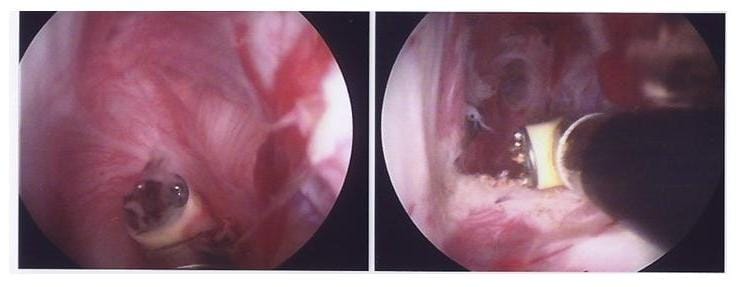

Bild die entzündete Gelenkkapsel wird in Schlüssellochtechnik gelöst

Arthrolyse: Die entzündete Gelenkkapsel wird in Schlüssellochtechnik gelöst. Links sieht man die verkürzte Kapsel, die rechts mit einem speziellen Instrument aufgetrennt wird. (Bilder: Orthopädie)